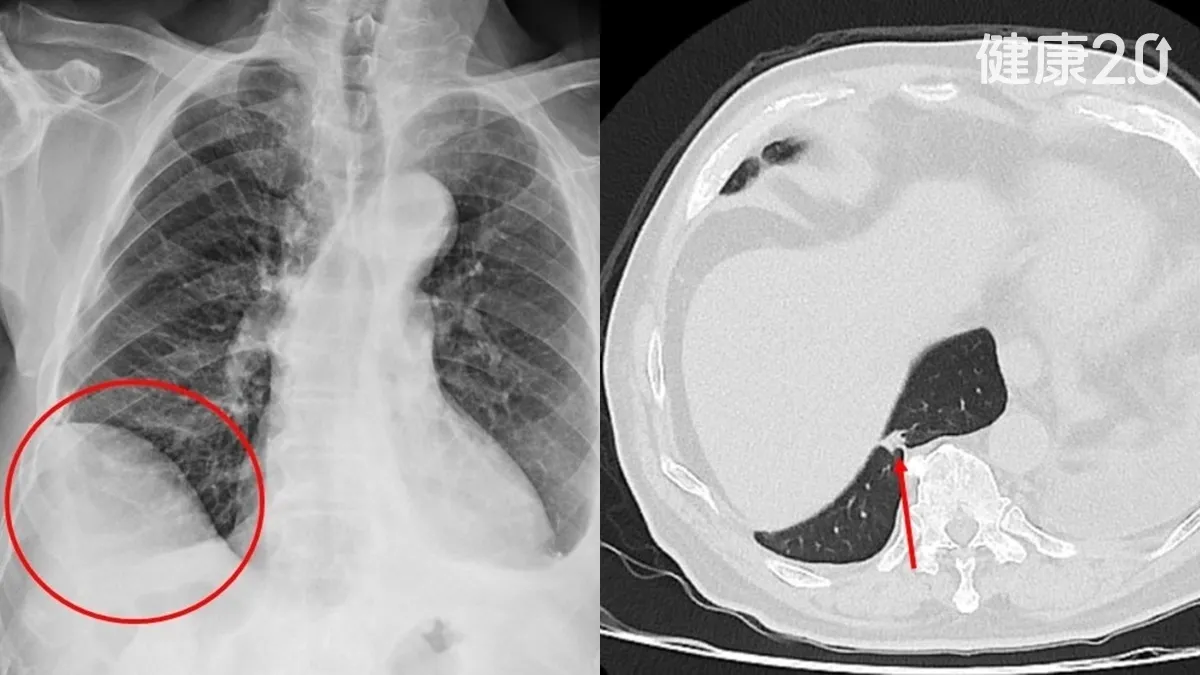

得肝癌了怎麼身體裡還有肺癌?一名75歲的吳先生原本正因為罹患肝癌,在仁愛長庚合作聯盟醫院接受治療,沒想到在治療期間進行追蹤檢查時,竟然發現右下肺長了一顆約1.2公分的新腫瘤。

因為懷疑是肺癌,肝膽腸胃科的主治醫師,便將吳先生轉介給胸腔及心臟血管外科廖啟耀主任看診,經醫療團隊與家屬討論後決定手術切除。

廖啟耀主任說明,吳先生非常幸運,因治療肝癌期間接受詳細追蹤檢查讓他得以及早發現病灶,證實為第一期肺癌。因為經過精確的手術切除後已將腫瘤完全清除,後續無需再進行放射治療或是化學治療。目前他的肝癌治療也相當順利,整體預後情形十分良好。